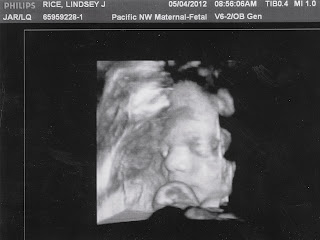

Before leaving the doctor's office that day, he gave us some 3D images of little sprout. As always, he had his hand up near his face, making it difficult to get a good shot. Before I knew it that crazy doctor was pushing on my belly telling him to move his hand. I watched the screen as our little boy moved his hand out of the way for just enough time to get one shot. We did this about three times because Mom kept laughing and messing up the picture. After the third time came this photo:

We also got to see right where his foot was resting against my insides- right where I get steady strong kicks throughout my day: